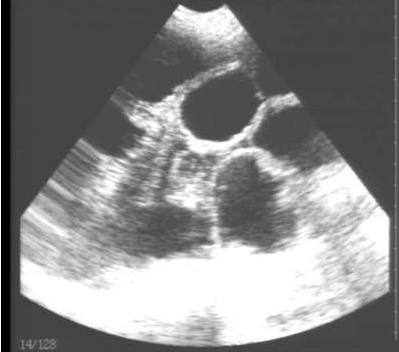

需要注意的是,出現(xiàn)云團狀必須雙側(cè)檢查加以確認.根據(jù)B超機顯示圖我們大致可以判斷孕齡.圖像呈橢圓或者卵圓形大致為30天左右孕齡;圖像呈橢圓形或者卵圓形外,有明顯發(fā)亮骨骼圖像大致為50孕齡左右;圖像囊胚消失,發(fā)亮處隱約可見竹節(jié)狀東西為成型胎兒骨骼,一般為后期80孕齡以后。一般B超機成像會出現(xiàn)三種顏色,白色、黑色、灰色。白色為密度較高的物體,如骨骼或者結(jié)實.黑色一般為液體,包括血液、羊水、組織間隙液體、炎癥病灶等。灰色一般為實質(zhì)性物質(zhì),如肌肉。

獸用B超機檢測母豬胎兒骨骼圖像

懷孕后期胎兒骨骼圖像